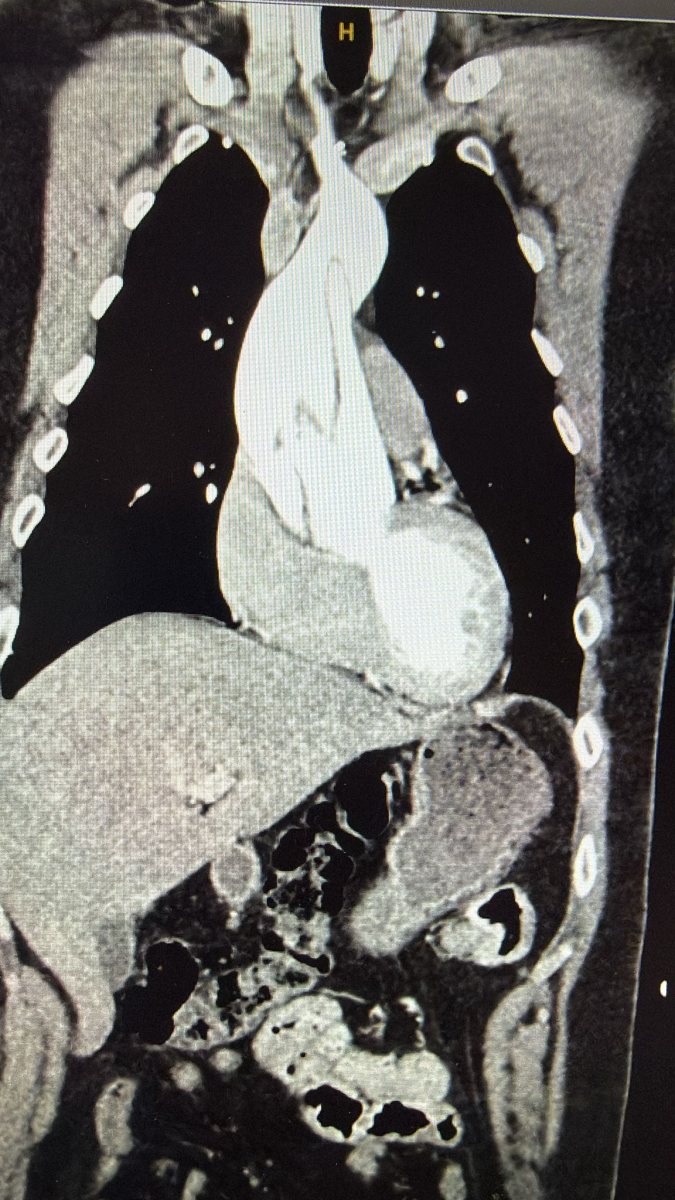

בליל ראש השנה תשס"ה, 16 בספטמבר 2004, הגיעה למרכז הרפואי שערי צדק אישה צעירה בשבוע ה-25 להריון כאשר היא סובלת מקרע מסכן חיים באבי העורקים.

בבדיקות שנעשו לאחר מכן אובחנה האם עם תסמונת מרפן (תסמונת תורשתית הפוגעת בין היתר בכלי הדם ובלב) כאשר הבן אובחן גם הוא עם אותה תסמונת גנטית.

בעקבות החמרה במצבו של א' שהובילה לחשש לנזק בדופן הלב, 21 שנים לאחר מכן, ב-26 בספטמבר 2025, הגיע א', כיום קצין ביחידה מסווגת בצה"ל, לשערי צדק לצורך ביצוע ניתוח דחוף.

א' מספר "ידעתי במשך השנים על סיפור הלידה המיוחד שלי, ועל התסמונת שיש לי. לא נתתי לה לעצור אותי בשום שלב בחיים. הייתי כל השנים במעקב אבל לא היו שינויים במצבי. 21 שנים אחרי, מספר ימים לפני שהייתי צריך לעבור בדיקת מעקב שגרתית חשתי בכאבים חריגים באופן קיצוני והגעתי לביה״ח שערי צדק. אבחון מהיר בביה"ח זיהה קרע באבי העורקים, ושוב הוזעק מביתו ד״ר פינק לניתוח חירום, שהציל את חיי בדיוק כמו שקרה 21 שנה קודם לכן שהציל את חייה של אימי".